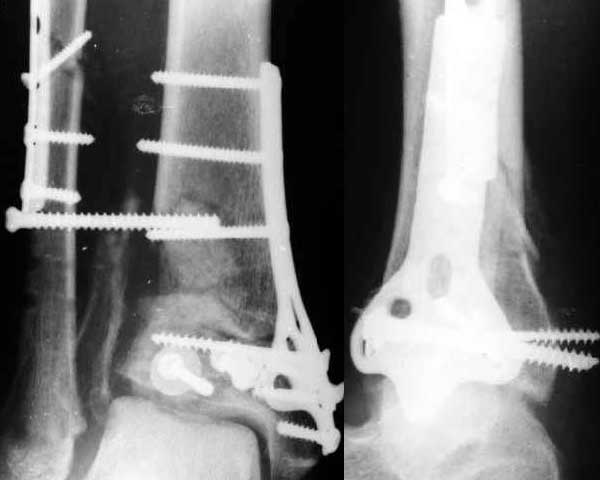

Полтора месяца назад мужчине 45 лет выполнена открытая репозиция дистального отдела большеберцовой кости и внутренняя фиксация (снимок 1).

На другой ноге - переломы нескольких плюсневых костей. Из-за сопутствующих урологических проблем через две недели перевели в другое учреждение, там был вынужден ходить с костылями с нагрузкой на обе ноги.При контрольной явке к нам через месяц обнаружилась несостоятельность фиксации (снимок 2). Какие выходы их положения можно тут предложить?

This is a BIG problem, that fortunately is somewhat less common now than 10 years ago. The fibula and a large piece of distal lateral tibia are now displaced laterally about 1 cm. It is difficult to assess how well reduced the tibia articular surface was and is. You might consider:

Yes. Looks like pure depression of the grafted metaphyseal part. Of course along with separation of the lateral aspect (plus syndesmosis and tibia).

Syndesmosis screw is pushing against the tibia and widening the Tibio-fibular space and Ankle Mortise.

невозможно достичь стабильной фиксации всех фрагментов особенно центрального и латерального отделов плафонда - что мы и имеем в данном случае: послеоперационная Рг - демонстрирует вроде бы анатомичную реконструкцию суставной поверхности, хотя, при более близком ассмотрении - сохраняется диастаз и смещение по высоте между Chaput tubercle и основным суставным фрагментом. Межфрагментарный винт, проведенный через м.б. кость в метафиз б.б., по всей видимости, не * зацепился* за медиальный кортекс и как результат этого все вернулось к тому же положению отломков, что и было изначально. Согласен с Александром Артемьевым, что внешняя фиксация в данной ситуации была бы предпочтительна: стержневая ( 2 Шанца в б.б. кость IV- VI уровни по Соломину и по одному винту в пяточную и таранную кости) или в аппарате Илизарова - дистракция по продольной оси б.б кости с встречно-боковой компрессией через м.б. и б.б. кости. Если состояние мягких тканей позволяет, то после устранения вальгусного наклона тарана можно выполнить костную пластику передне-наружного дефекта б.б кости. I do agree with Nikolaj about potential risk of developing skin flap problems fortunately first procedure did lead to any of known complications so I would not challenge it again at this stage. Once I have used subcutanous plating of tibial pilon fracture from anterior approach. it worked quite well. The only disadvantage is X-ray loading during the surgery. I will appreciate if collegues will share their experience of utilising such